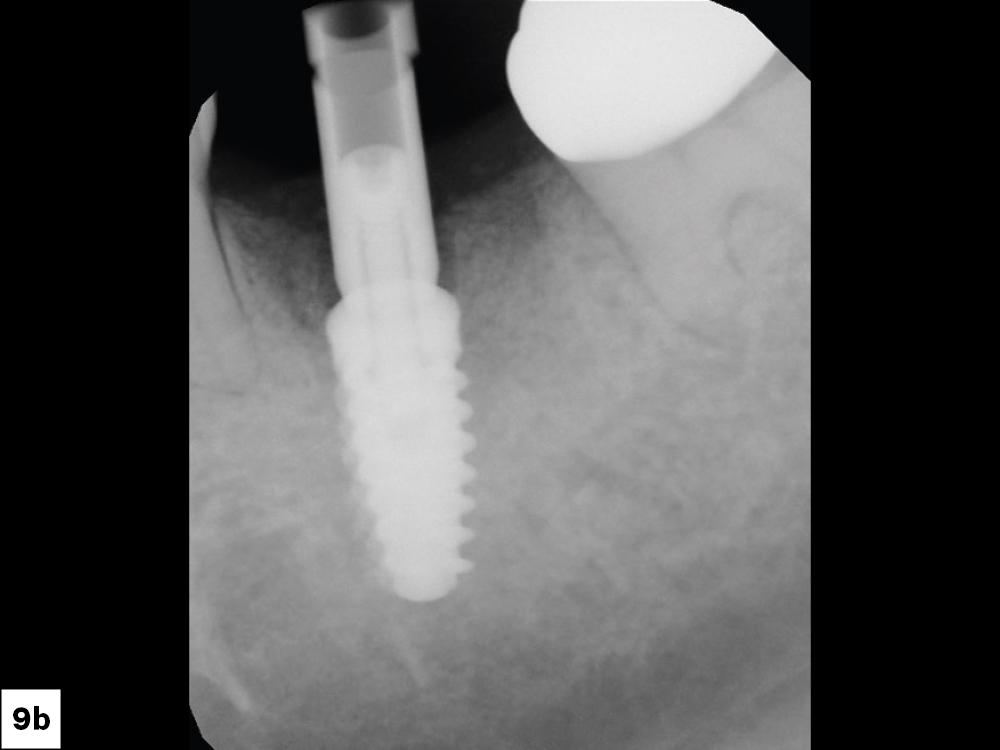

In-office milling is a quickly evolving option for the modern dental practice. With the introduction of a same-day screw-retained option, BruxZir® NOW SRC milling blocks, there’s even more opportunity for optimizing single-unit restoration workflows. In this case study, I’ll demonstrate how this product can be used as part of an efficient workflow for tooth replacement in the posterior. When combined with guided surgery and in-office crown design, this procedure offers reliable results while saving money and significantly cutting down on chair time for dentists.